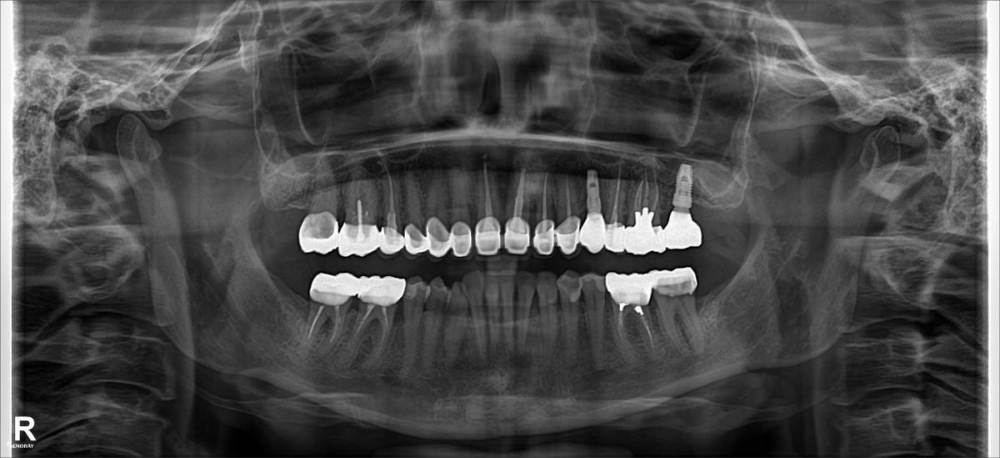

Добрый день, честно говоря не думала, что вновь вернусь на этот форум с новыми проблемами. Итак, что имеем до протезирования: десневая улыбка, глубокий прикус, старые коронки и мост, старые пломбы, отсутствие двух зубов, кое где глубокие десневые карманы (преимущественно 6-7 справа), решили навести красоту. В 2020 году провели замену старых коронок, полное протезирование верхней челюсти+установку двух имплантов, костную и десневую пластики. Через полгода доустановили жевательные зубы на верх/низ. До протезирования были предложены брекеты, но по ряду причин я отказалась, видимо зря.

Паралелльно с этим начались проблемы с 2кой слева, возникли болевые ощущения в зоне десны, сделав снимок, обнаружили стремительную убыль костной ткани на обех двойках, началось гноетечение преимущественно слева. Между 1-2 слева между коронками появилась щель, зубы пока не особо подвижны. По хорошему эти зубы нужно удалять и ставить импланты (хотя уже сейчас по моему сложная картина для их установки), но врач хочет максимально сохранить зубы, поскольку после удаления зуба может начаться атрофия десны (не факт, но риск есть), оголяться корни соседних зубов, нужно будет делать десневую платику, бояться рубцов. Направили к парадонтологу, был проведен закрытый кюрретаж, пила антибиотки, положительных результатов это не дало.

Началось гноетечение еще в трех зубах снизу (6,7 справа, между 2-3), опустилась десна на 7 слева, но тут виной скорее всего глубокие десневые карманы, на 7м справка после замены коронки он стал еще больше потому что коронка встала глубже. Между 2-3 сделали с хирургом открытый кюрретаж. 7 ку справа скорее всего удалять.

По направлению своей клиники снова обратилась к другому парадонтологу, первый вопрос был: как при такой картине были установлены коронки? Но возможно у вас до этого такого не было (снимки старые я не могу найти к сожалению). Ставили ли вам ранее диагноз парадонтоз? Нет не ставили.

Сейчас будем делать парадонтологическую чистку, сдала кучу анализов, планируются новые антибиотики, далее закрытый кюрретаж. Больше всего врача беспокоит убыль кости на двойках и почему эту происходит. Склоняется к проблемам с прикусом (с двигающейся челюстью), может где то есть супер контакт (про него мне уже говорил и первый пардонтолог и ортопед, но мы его не нашли).

Снимок.jpg